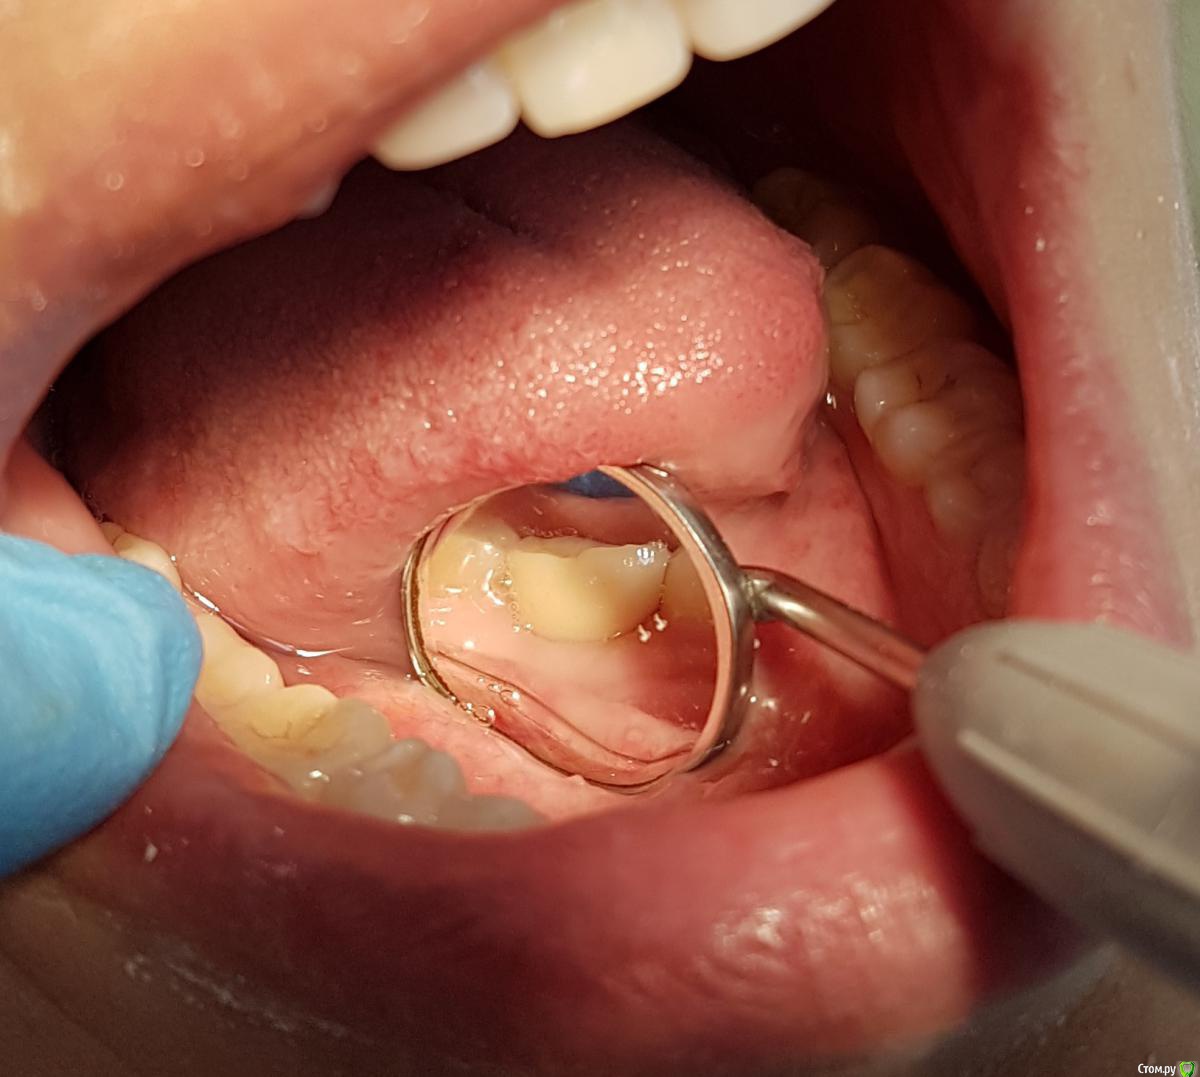

Kostoprav Опубликовано 22 июля, 2017 Автор Поделиться Опубликовано 22 июля, 2017 финиш 2 Ссылка на комментарий

AlexanderGudkov Опубликовано 23 июля, 2017 Поделиться Опубликовано 23 июля, 2017 финиш20170722_171248.jpg20170722_171318.jpgЧотка!)) Ссылка на комментарий